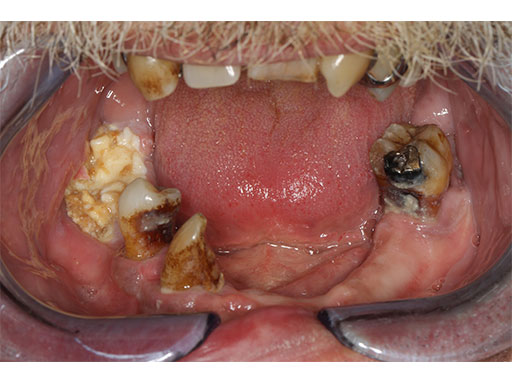

A 58-year-old male patient had oral cancer (T4n0m0) infiltrating the alveolar process and the anterior border of the ascending ramus (Fig 2). The treatment plan involved resection, bilateral neck dissection (levels I to III), and primary mandibular reconstruction with a right osteomyofasciocutaneous fibula flap.